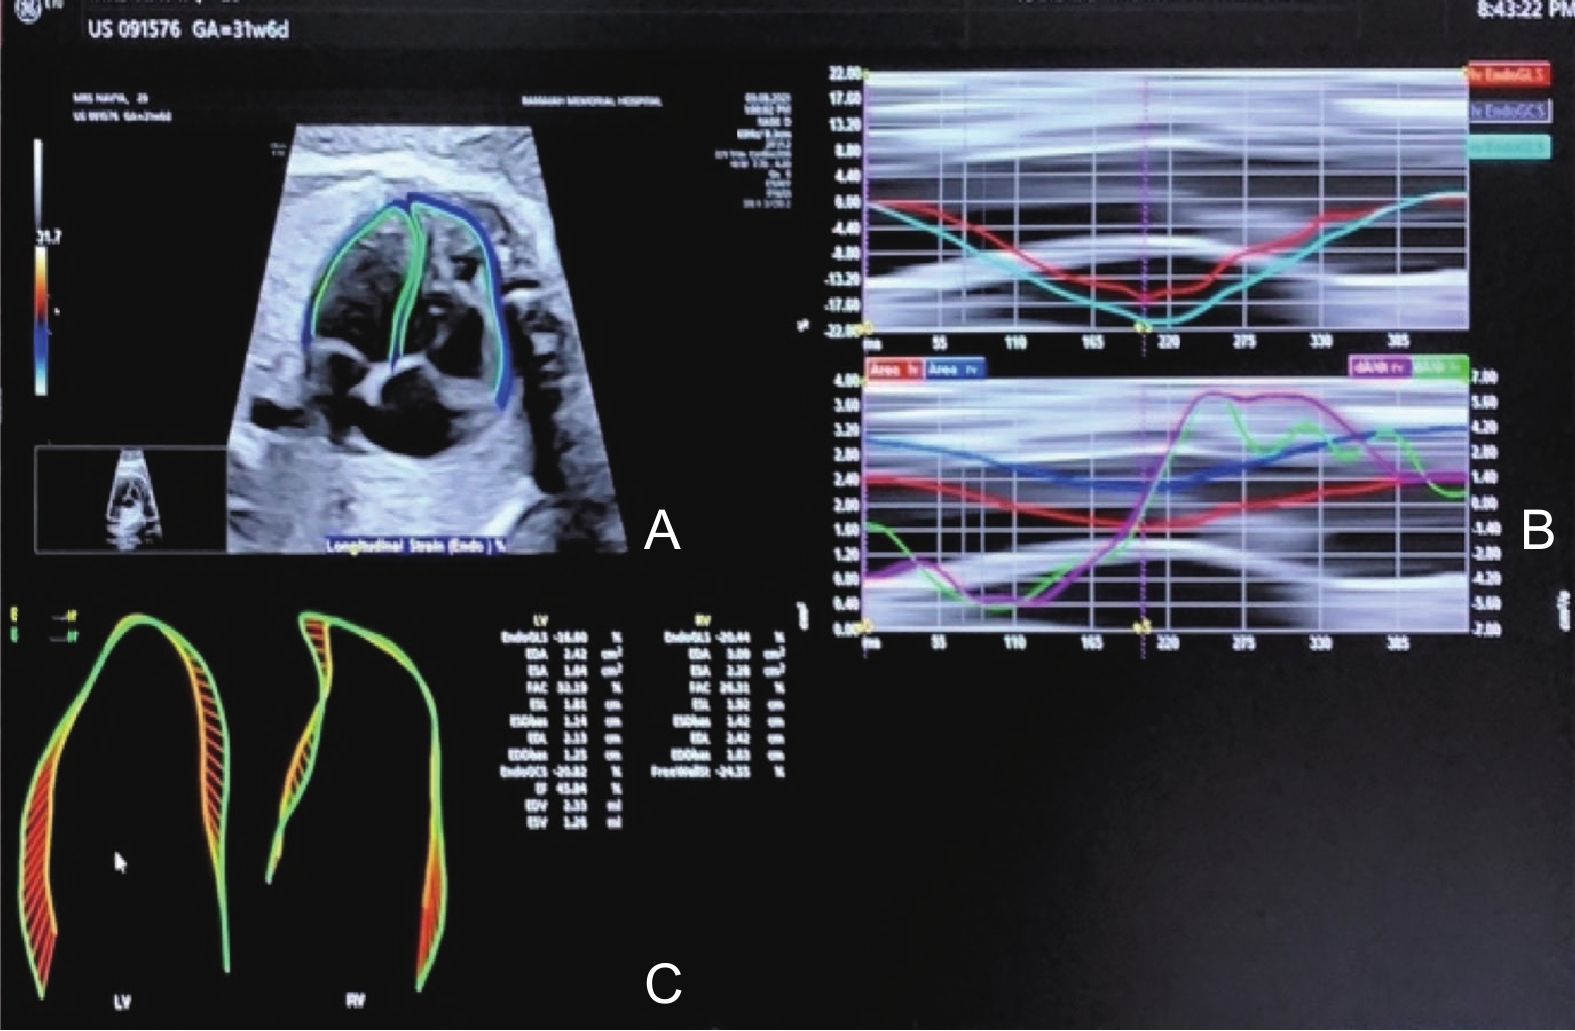

Figure 5

Speckle tracking- Fetal HQ. (A) Marked myocardial region of interest in the left ventricle (LV) and right ventricle (RV); (B) Deformation vectors in the LV and RV; (C) LV and RV global longitudinal strain (GLS) analysis. (Images were acquired on E10 Voluson ultrasound machine and analysed using FetalHQ software)"